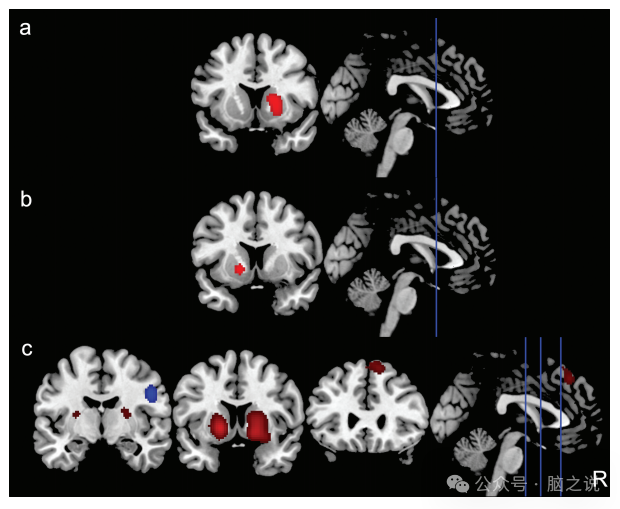

所有的测量。与对照组相比,FEP组在右侧纹状体[峰坐标(x,y,z) = 18,14,0]、左侧纹状体[峰坐标(x,y,z) =−16,10,−2]、双侧额上回/额中回(SFG/MFG)[峰坐标(x,y,z) =−4,36,46]的AIFF/fAIFF值和ReHo值显著增高。我们还观察到右侧中央前回和右侧额下回(IFG)的自发性脑活动减少[峰坐标(x,y,z) = 50, - 4,30](图2,补充表S.4-S.6)。当在报告同一样本的多个测量值的文章中仅纳入每个研究的一个测量值时,以及当我们仅纳入使用多重比较校正的研究时,这些结果未发生变化。

图2 与健康对照组相比,FEP的CBMA值有内在活性改变。